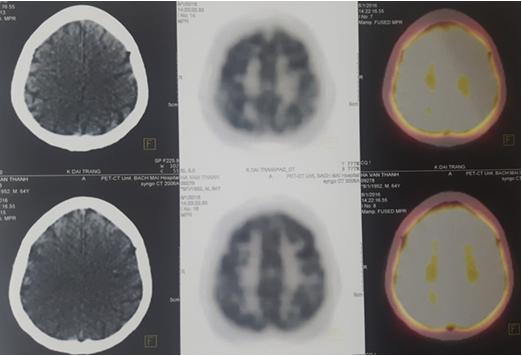

Hình 5: Hình ảnh PET/CT não sau điều trị

Nhu mô não hấp thu FDG đồng đều, không thấy u.

So sánh kết quả trước và sau điều trị:

Hình 6: Hình ảnh so sánh kết quả PET/CT trước và sau điều trị